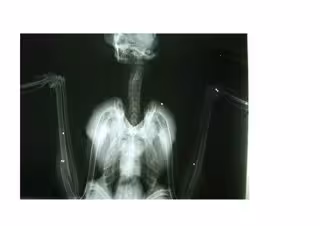

Radiografía de cernícalo con perdigonazos

El pájaro, que se ha liberado en el bosque de La Marquesa, dentro del Espacio de Interés natural Tamarit-Punta de La Mora (Tarragona), había sido herido por diversos impactos de perdigón y presentaba diversas fracturas.